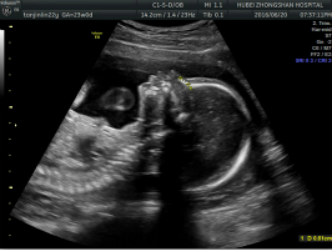

2.妊娠18周~24周超声检查;主要进行胎儿结构畸形的系统筛查。此阶段是观察胎儿结构和诊断胎儿畸形黄金时段,我们建议所有孕妇在此阶段务必接受一次超声检查。

2.妊娠18周~24周超声检查:主要进行胎儿结构畸形的系统筛查。此时期胎儿各器官已发育成熟,系统产前超声检查可记录胎儿各器官结构包括头颅、面部、胸腹腔、心脏、肝脏、双肾、肢体及胎盘等结构,可发现大多数胎儿结构畸形。此阶段是观察胎儿结构和诊断胎儿畸形黄金时段,我们建议所有孕妇在此阶段务必接受一次超声检查。